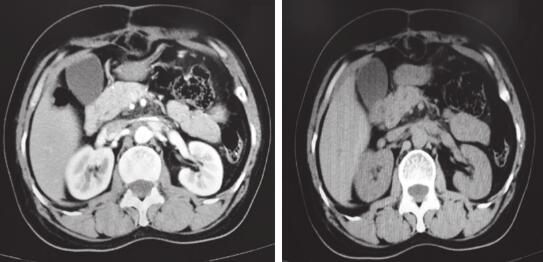

全腹增强CT(图2):腹主动脉前方肿块,肿块截面大小约7.7cm×4.1cm,部分包绕腹主动脉、双侧肾动脉近段、左肾静脉,左肾上腺外支局部分界欠清,考虑副神经节瘤的可能性大。

图2 全腹部增强CT检查